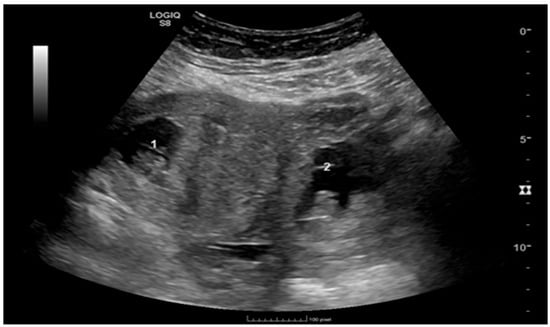

Pregnancy (HP), defined as the coexistence of intrauterine and ectopic gestations, is a rare condition, especially in spontaneous conception, but it is a life-threatening obstetric emergency when rupture occurs, with a reported maternal mortality rate of 0.03%. Diagnosis is often delayed because confirmation of an intrauterine pregnancy can mask clinical signs of a concurrent ectopic gestation. Early recognition and prompt surgical intervention are therefore critical to maternal safety and preservation of intrauterine viability. This case highlights the diagnostic challenges and successful management of a spontaneous ruptured heterotopic pregnancy. Case presentation: A 34-year-old Middle Eastern woman, gravida 4, with a spontaneous conception, presented with sudden severe lower abdominal pain and signs of acute hemoperitoneum (hypotension, tachycardia, and marked peritoneal signs). Transvaginal ultrasound demonstrated a viable intrauterine pregnancy at 9 weeks 4 days gestation, together with a ruptured left tubal ectopic pregnancy of similar gestational age. The patient underwent urgent laparoscopic left salpingectomy with evacuation of approximately 1200 mL of intraperitoneal blood and clots. Postoperatively, she developed significant anemia (hemoglobin drop from 11.2 g/dL on admission to 6.5 g/dL) requiring transfusion of four units of packed red blood cells. Serial ultrasonographic follow-up confirmed ongoing viability of the intrauterine pregnancy, which ultimately resulted in a live birth at term. Progressive resolution of the postoperative pelvic hematoma was also noted. Conclusions: Ruptured heterotopic pregnancy remains a diagnostic and therapeutic challenge. This case, along with a synthesis of the contemporary literature, demonstrates that a high clinical index of suspicion, timely ultrasound diagnosis, and immediate minimally invasive surgical management are paramount. Furthermore, rigorous postoperative monitoring and resuscitation, including targeted transfusion, are essential to achieve maternal stabilization while allowing continuation of a viable intrauterine pregnancy, with reported live birth rates exceeding 70% following timely intervention. Full article